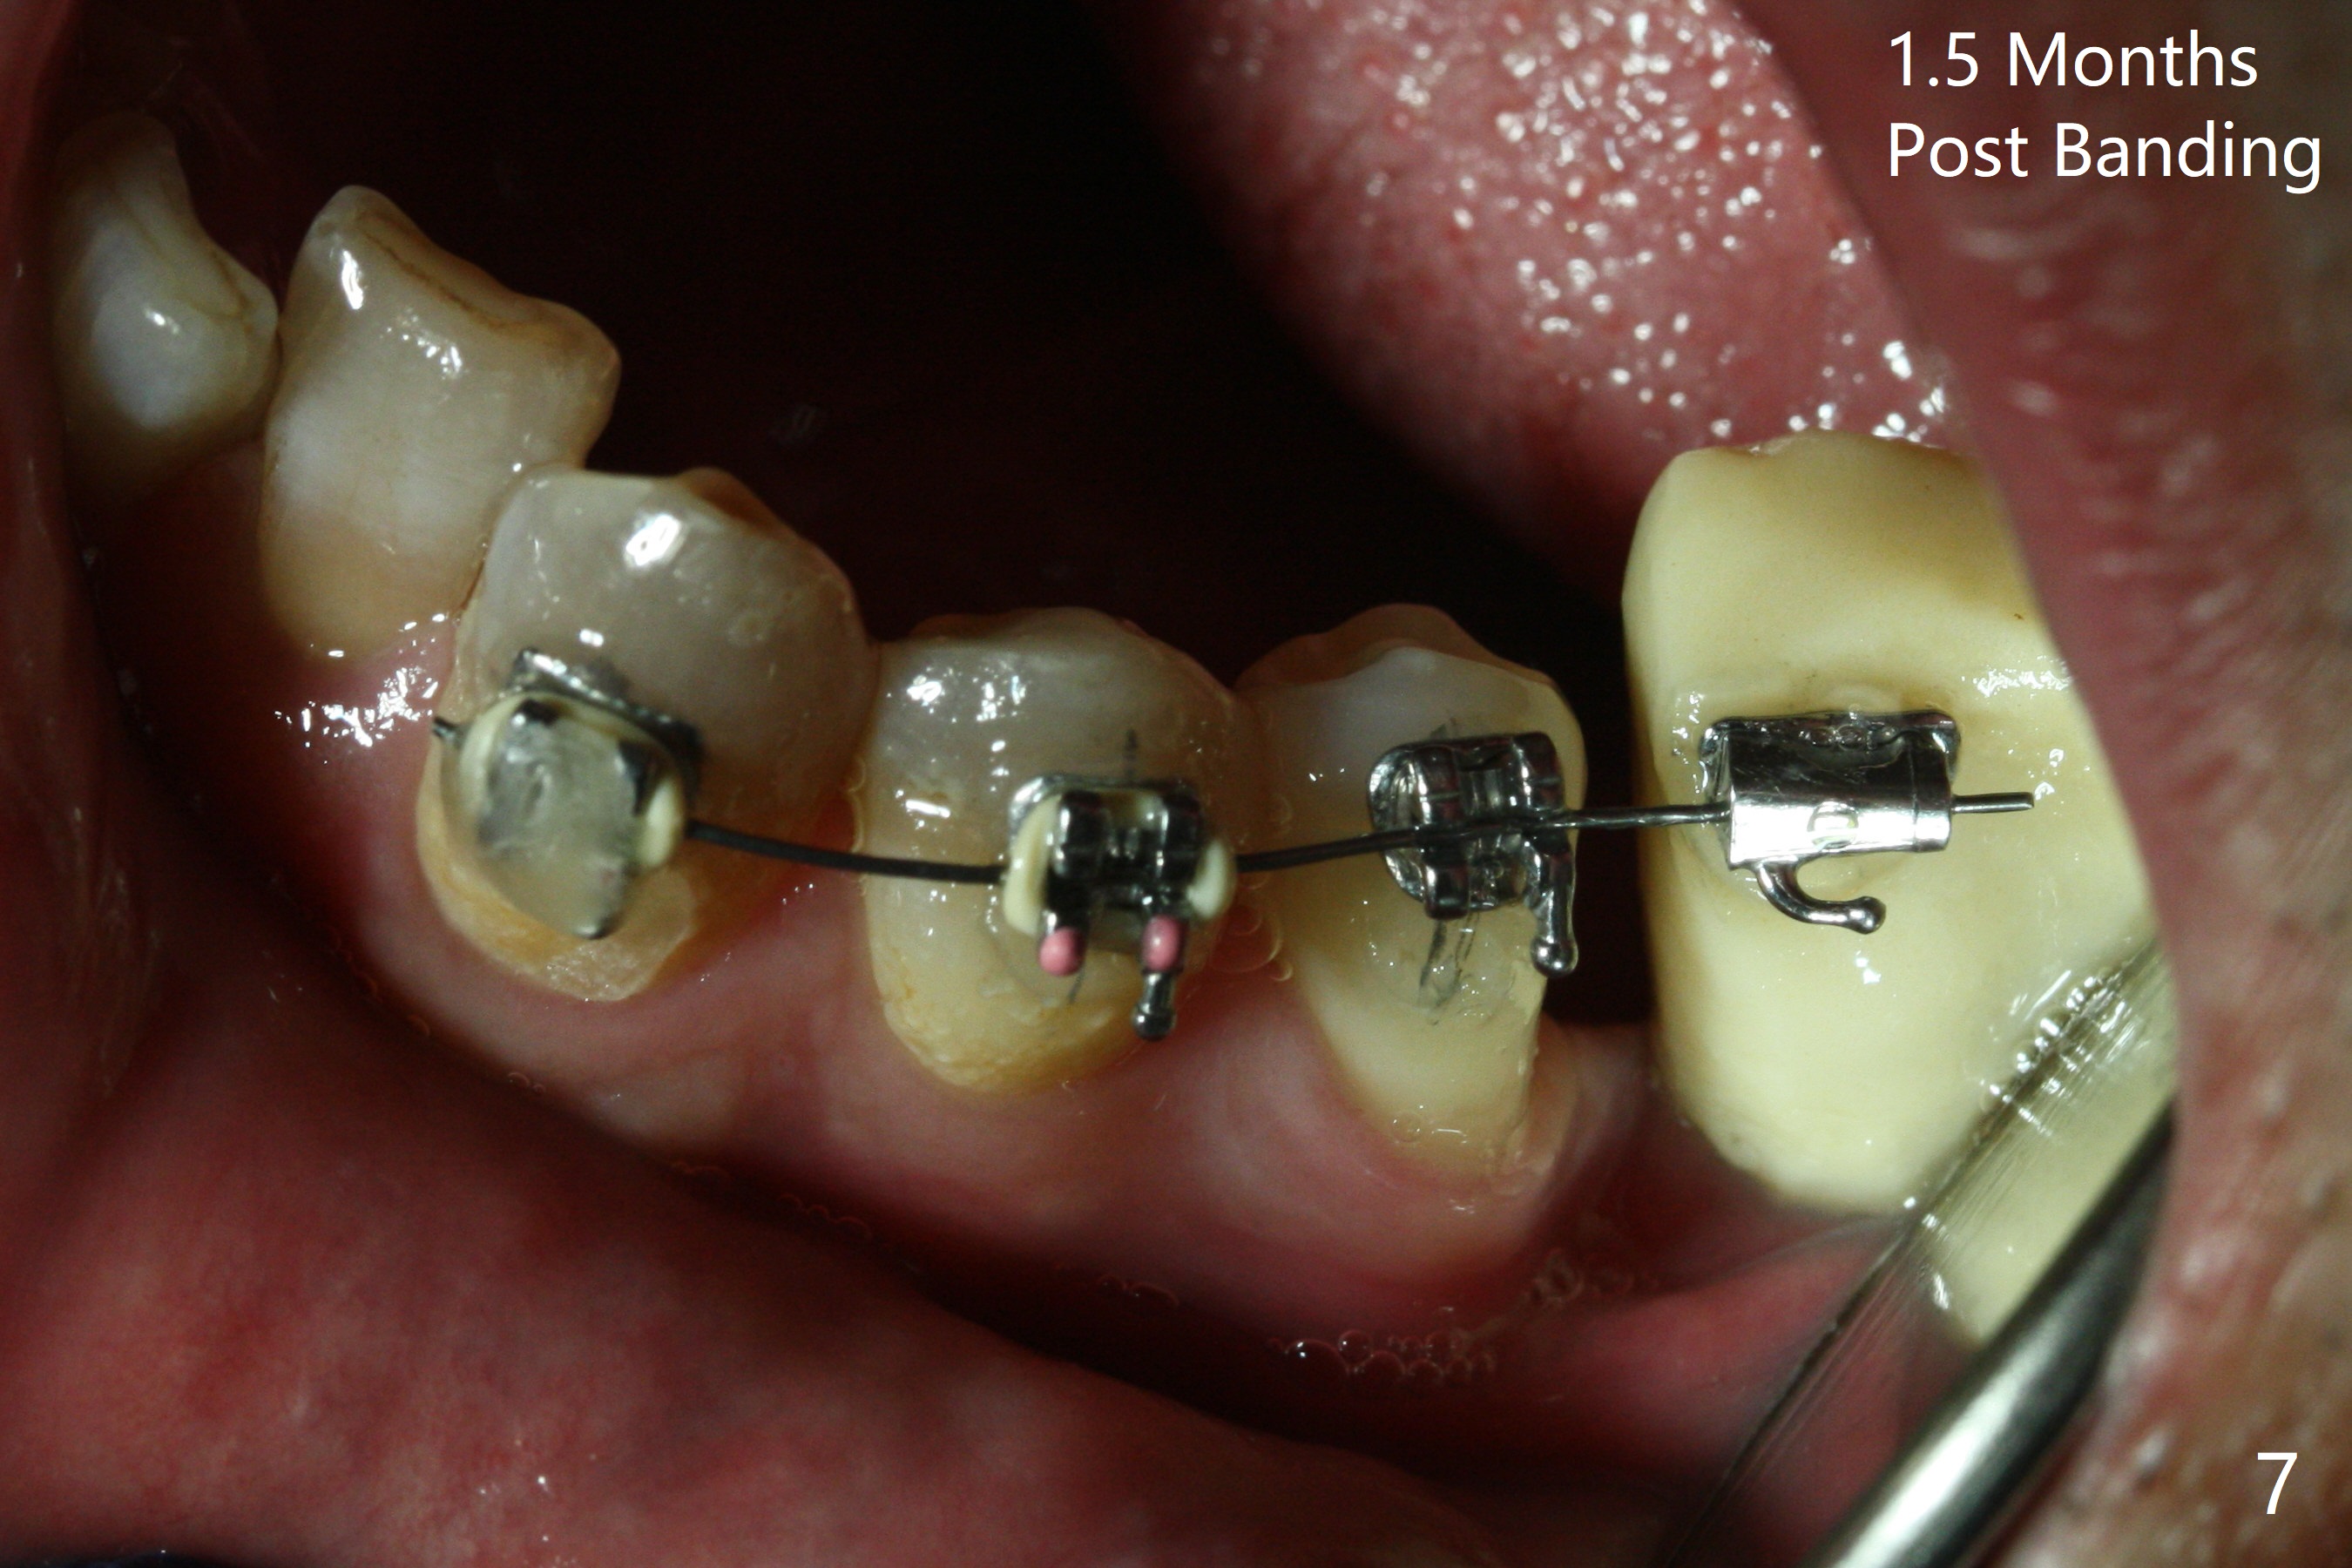

Two weeks post provisionalization over implants at #18 and 19 (4.5 months postop), acrylic is added to the provisional (Fig.1 *) and composite is placed on the other side (Fig.2 *) for clearance (Fig.3). Six days post bracketing, the diastema between LL5 and 6 decreases (Fig.4 between arrows, as compared to Fig.3), suggesting uprighting and distalization of the affected tooth. The diastema increases by trimming the mesial surface of LL6 provisional (Fig.5 *) prior to power chain placement. More acrylic is added to the occlusal surface of LL 6 and 7; more composite to that of UR3 (as compared to Fig.2) for clearance. Power chains change every week. LL5 is uprighted and distalized 1.5 months post banding (Fig.6,7 (14 niti)). Anterior brackets will be placed to correct LL2 cross bite next visit. Three weeks post open coil spring (5 months post initial banding), there is a space between LL2 and 3 (Fig.8) and between LL3/4 (Fig.9). The latter reduces instantly post power chain between LL3 and 6 (Fig.10). There is enough space for LL2 and sling shot is used to correct the cross bite 6.5 months post initial banding (Fig.11). The cross bite is corrected in 1.5 months after occlusal clearance is established (Fig.12). The lower left alignment is within normal limit, although in cross bite with the opposing dentition, immediate post molar crown cementation (Fig.13).